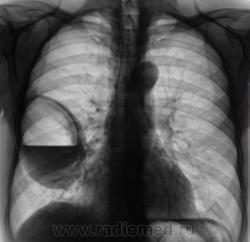

Лаборант «с флюорографа» пригласил посмотреть произведенную флюорограмму.

Лаборант «с флюорографа» пригласил посмотреть произведенную флюорограмму.роизвели рентген

Произвели рентгенографию в стандартных проекциях.

Флюорограмма 2009 года.

сильно похоже на нагноившуюся кисту...

Она и есть.

Но, пациент жалоб не предъявляет...

Киста, точно киста. Был пациент на консультации у торакальщиков, будут готовить к плановой операции.